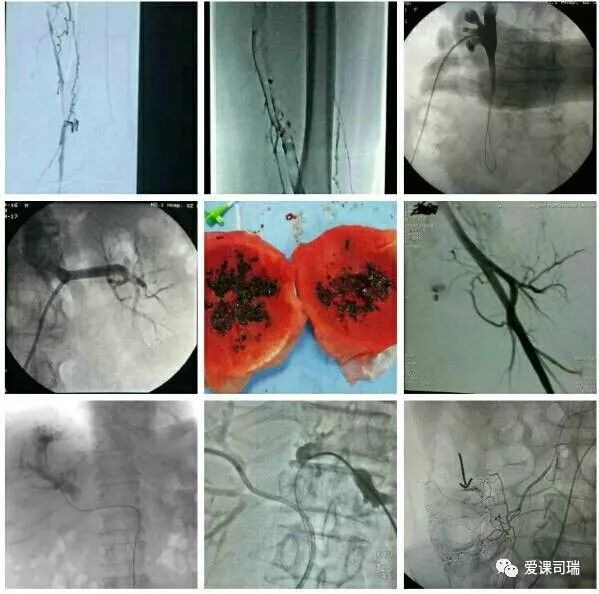

1.有影像设备的引导:在能够“看穿身体”的影像设备帮助下,不需要切开人体,就能看到体内脏器和病变,实现“可视化”。

3.诊断与治疗相融合:介入医生能够通过影像设备直接看到病变,疾病的诊断就很容易明确,随即又可立刻转入治疗过程,实现“诊断治疗一体化”或“诊治一条龙”。整个过程都看得见,治疗过程中又可继续诊断,如果判断效果还没有达到预期,立即追加治疗也非常方便。

概括地说,介入诊疗有以下优势: 1.可以远道施术:借助于导管等器材,可以从对病人最有利、远离病变的部位入手,将治疗器材送达病变局部,再施行精细的治疗。比如,头部有病,我们可以方便地从大腿跟部进管,经血管插管到头部去,从而避免直接切割或穿刺头部。 2.创伤轻微,容易耐受:借助于影像设备这“第三只眼睛”的引导,无须开刀即能清晰显示病变部位,从而进行准确的治疗操作。 3.可重复性强:由于创伤小,不会造成局部的粘连和组织缺损,因而可以多次反复地进行治疗,直到病变完全康复为止。 4.定位准确:有影像设备作实时的引导和监控,没有视觉盲区,因而可以“指哪打哪”。 5.疗效高、见效快:对很多病变可以起到“立竿见影”的效果。 6.并发症发生率低:也就是说安全性高,由上述多种优势的综合作用所致。 7.方便联合应用多种介入技术:介入诊疗技术种类繁多,各有特色和优势,可以方便地联合应用,取长补短,从而进一步增强治疗效果。

“介入”的应用范围涵盖了头颈、胸腹、四肢等各个部位,涉及神经、心血管、呼吸、消化、泌尿生殖、骨关节等各个系统器官的病变诊治。

介入放射学按诊治目的可分为介入诊断学和介入治疗学,按涉及学科可分为神经介入、心血管介入、肿瘤介入、妇产科介入等学科分支;介入诊疗技术按进入途径则可分为血管性和非血管性两大类介入技术。